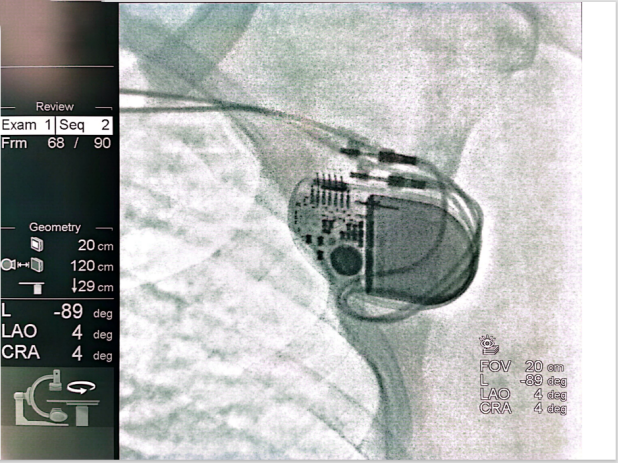

同时患者伴有脊柱疾病、脑梗等病史,充分考虑患者未来明确有3.0T场强MRI检查需求。因此,为患者选择植入雅培3.0T核磁兼容双腔起搏器PM2282。手术分别将右房、右室起搏导线分别植入于右心耳及右室间隔部,术中参数测试良好。

术中最终留影图

患者植入PM2282起搏器后,可接受1.5T和3.0T核磁共振成像全身检查,且核磁共振检查时无扫描部位和体位的限制,无MRI扫描时长的限制,实现全身无限制核磁共振兼容。

PM2282是一款体积小、厚度薄、重量轻的起搏器,仅6mm厚度更加适合皮下脂肪较少的亚洲人群。且配有术中无线遥测功能,必要时可在术中和平时为医生提醒患者的情况。不耗电的事件前腔内电图记录(Pre-EGM功能),更可以为医患提供更多证据和保护。另外,该起搏器也优化了电路设计,改进了电池,使得起搏器具有超长的使用寿命,能够减少患者更换的次数,降低感染风险,为患者一直保驾护航。